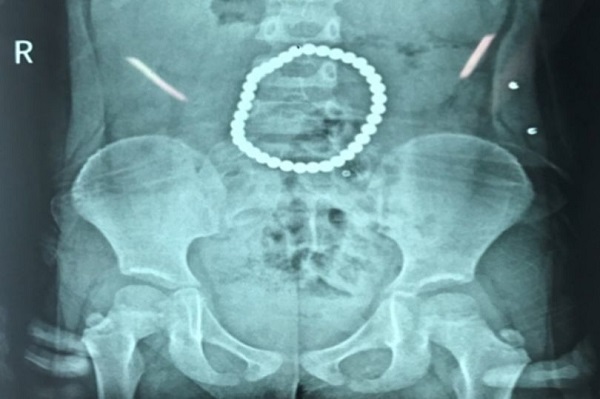

Hình chụp phim cho thấy chuỗi nam châm nằm trong người bé gái. |

Dạ dày của 1 bé gái 3 tuổi đã bị xé thủng 5 lỗ sau khi 37 viên nam châm hình cầu hút nhau hợp thành một vòng tròn trông giống như một chiếc vòng đeo tay.

Các bác sĩ tại bệnh viện Nhi đồng Hồ Nam tại Trường Sa, Trung Quốc, đã phát hiện ra các món đồ chơi này khi ba mẹ bé gái đưa em đến bệnh viện vào tuần trước, sau những cơn đau bụng dữ dội.

Hình ảnh chụp phim từ bệnh viện cho thấy các viên bi đồ chơi hiệu BuckyBall đã hút nhau bên trong dạ dày cô bé và tạo thành một vòng tròn.